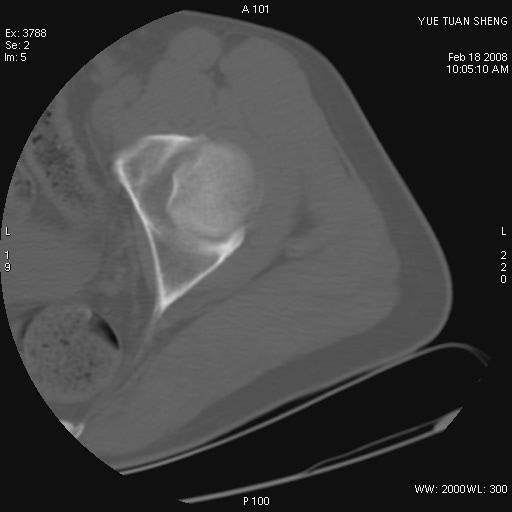

患者,男,56岁,左髋部疼痛1个月,x线:左股骨头高密度影,性质待定,右侧正常。左髋ct如图

左股骨颈区椭圆形磨玻璃样影,边缘明显硬化环环绕,其内见斑点状类钙化高密度影考虑 良性骨病-----骨纤,骨化性纤维瘤,内生软骨瘤。